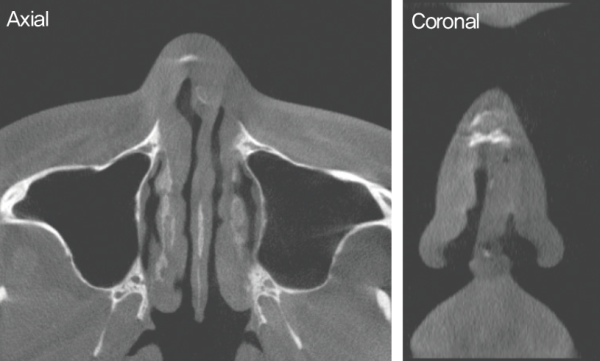

수술 전 CT. 비중격 만곡이 관찰되었다. 또한 비중격 골부에서 좌측으로의 만곡과 비중격 손상으로 인한 안장코 변형이

확인되었다. 측면에서는 이전 수술로 인한 비중격 소실이 관찰되었다.

수술 전 CT. 좌측 미단부에서 심한 만곡으로 인한 비밸브 협착이 관찰되었다.

내원 당시 시행한 CT 상 비중격 미단부와 상단부 연골부의 좌측으로의 만 곡, 비중격 손상에 의한 안장코 변형도 보였다.

비익연 골의 내전과 비중격 좌측 미단부의 변형으로 인해

좌측 비밸브에서의 협착도 관찰되었다.